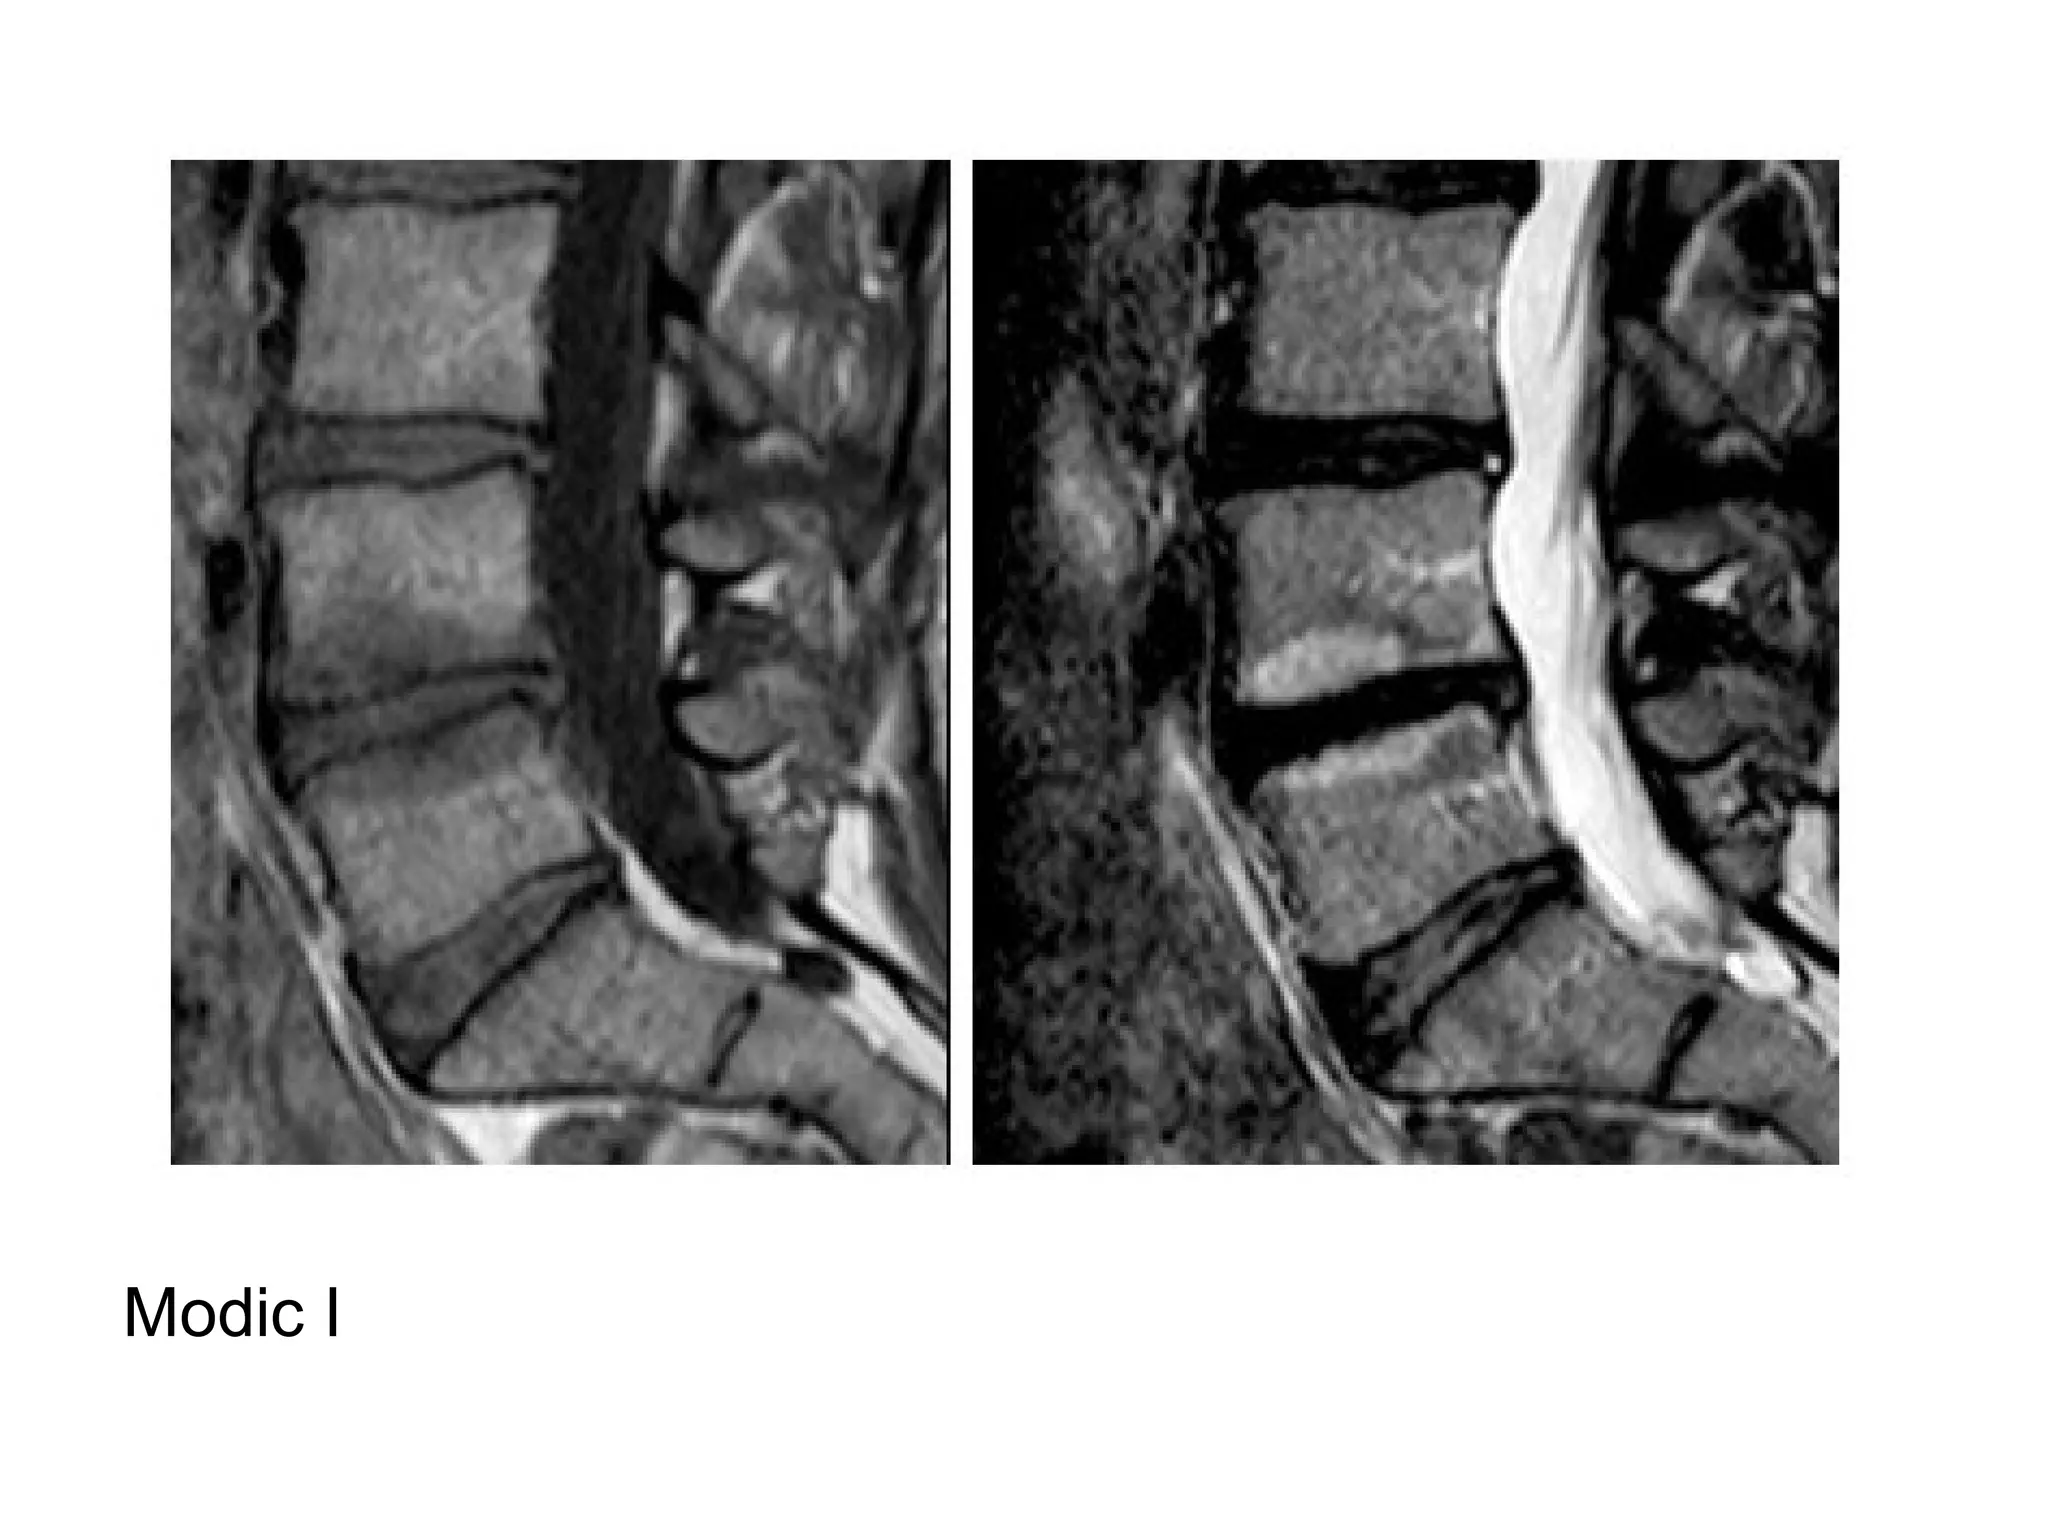

a) Modic I : dark T1 / bright T2 (vascular tissue

ingrowth)

b) Modic II : bright T1 / bright T2 (fatty change)

c) Modic III : dark T1 / dark T2 (sclerosis)

Modic , T1 & T2

Modic I